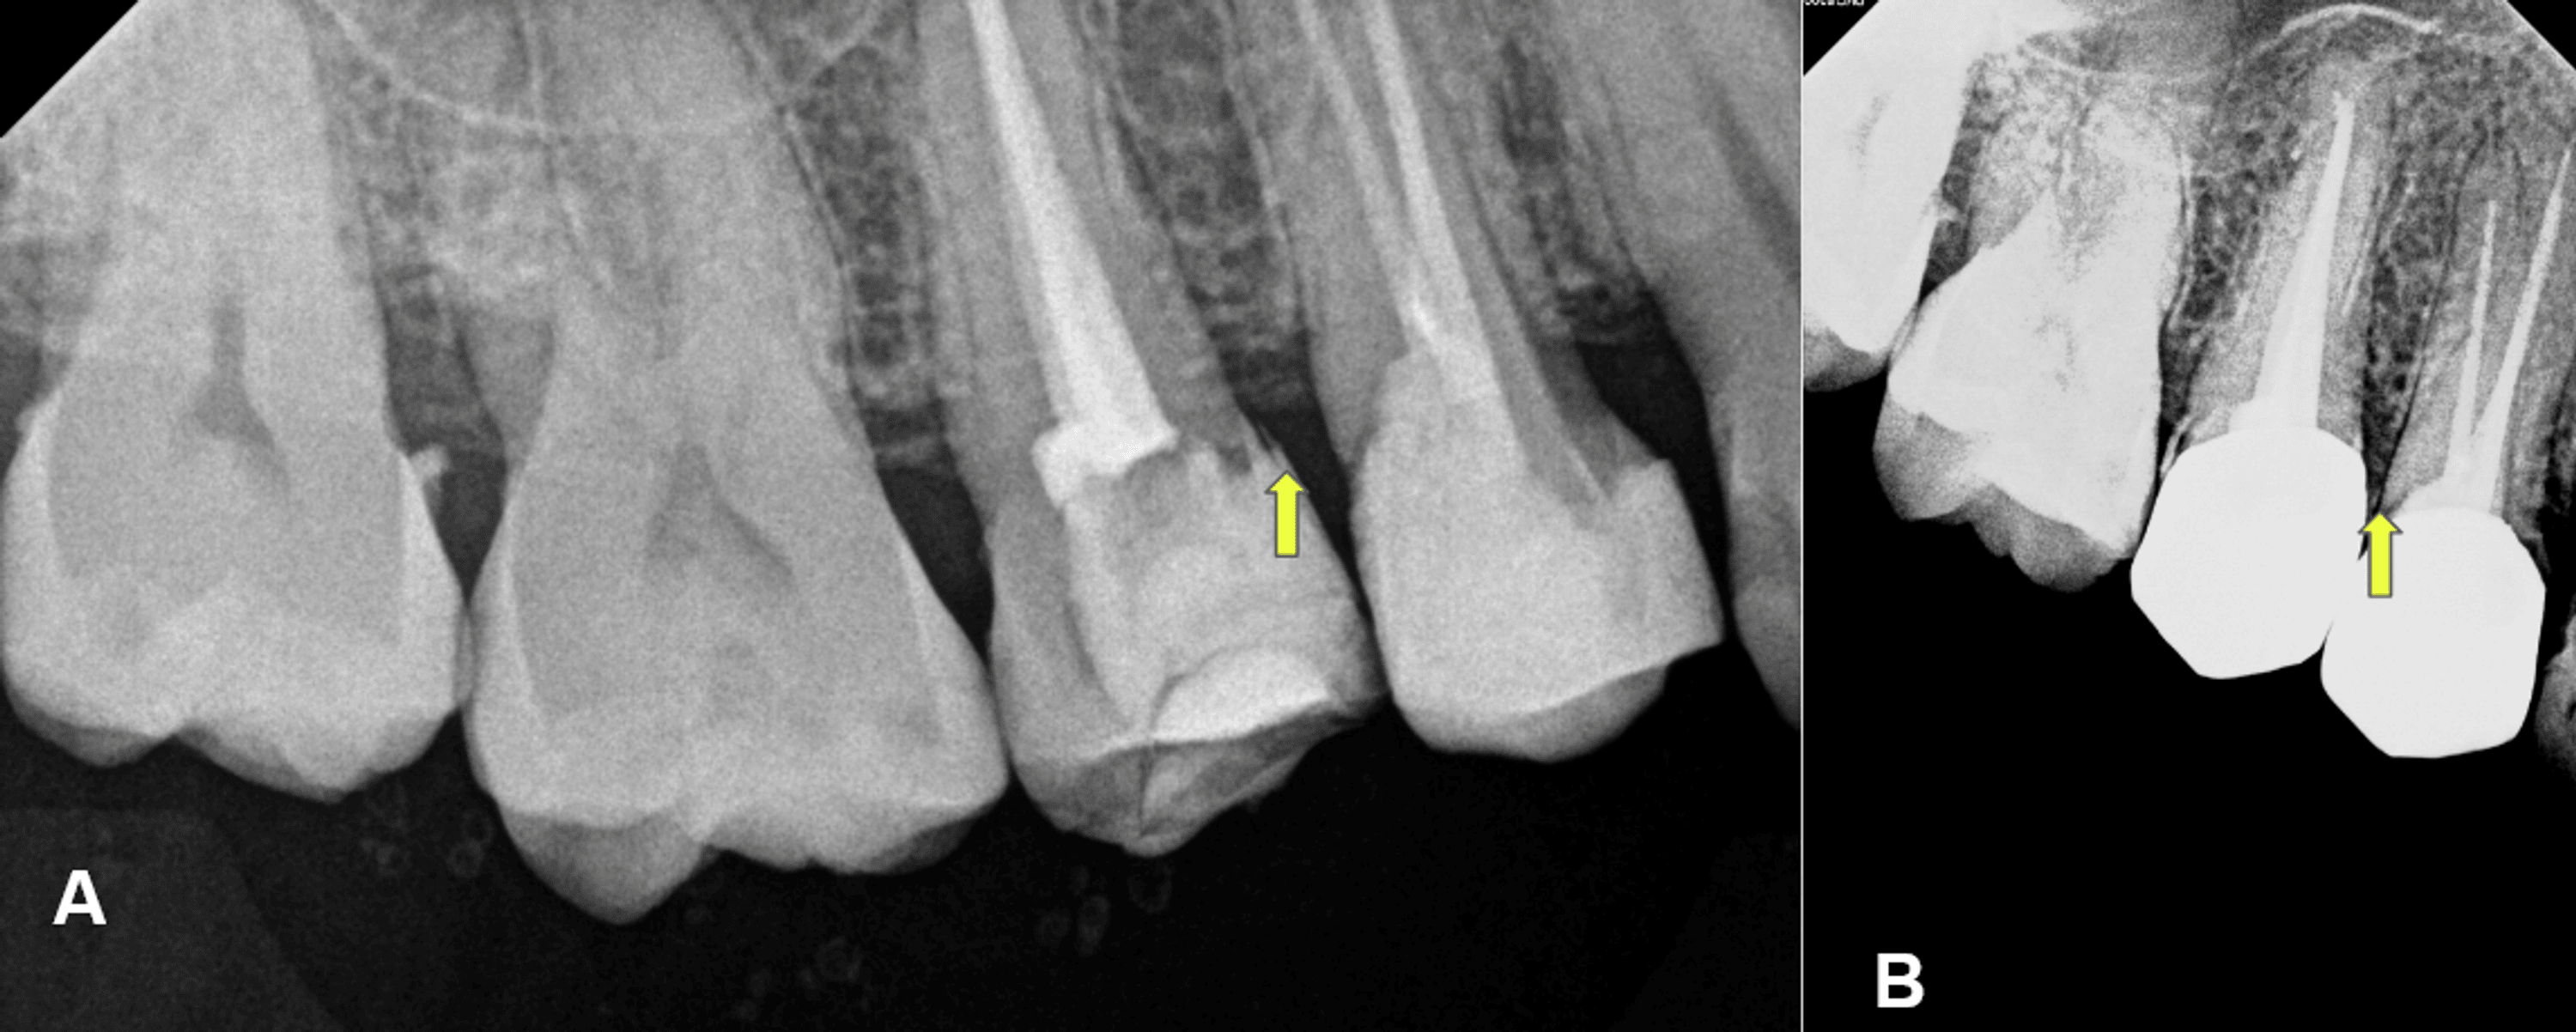

Biologic Width Violation . The supracrestal tissue attachment (scta) is the new terminology for biologic width. There are several reasons why this biologic width may be violated when a crown prep is made. If the tooth has fractured, the. Scta is defined as the physiologic dimension. Biologic width is the dimension of space that the healthy gingival tissues occupy above the alveolar bone. Correction of biologic width violations if there is less than 2 mm from restoration’s margin to marginal bone, clinical. Relevant publications regarding biologic width, its violation and management were identified up to august 2011 using manual and electronic. Discusses about biologic width and its significance, factors causing encroachment of biological width, evaluation and management of. The signs of biologic width violation are: Chronic progressive gingival inflammation around the restoration, bleeding on probing, localized.

Chronic progressive gingival inflammation around the restoration, bleeding on probing, localized. The signs of biologic width violation are: The supracrestal tissue attachment (scta) is the new terminology for biologic width. Discusses about biologic width and its significance, factors causing encroachment of biological width, evaluation and management of. Biologic width is the dimension of space that the healthy gingival tissues occupy above the alveolar bone. Scta is defined as the physiologic dimension. Relevant publications regarding biologic width, its violation and management were identified up to august 2011 using manual and electronic. If the tooth has fractured, the. Correction of biologic width violations if there is less than 2 mm from restoration’s margin to marginal bone, clinical. There are several reasons why this biologic width may be violated when a crown prep is made.

Biologic Width Violation Biologic width is the dimension of space that the healthy gingival tissues occupy above the alveolar bone. Relevant publications regarding biologic width, its violation and management were identified up to august 2011 using manual and electronic. The signs of biologic width violation are: The supracrestal tissue attachment (scta) is the new terminology for biologic width. Correction of biologic width violations if there is less than 2 mm from restoration’s margin to marginal bone, clinical. Biologic width is the dimension of space that the healthy gingival tissues occupy above the alveolar bone. Discusses about biologic width and its significance, factors causing encroachment of biological width, evaluation and management of. There are several reasons why this biologic width may be violated when a crown prep is made. Chronic progressive gingival inflammation around the restoration, bleeding on probing, localized. Scta is defined as the physiologic dimension. If the tooth has fractured, the.

foudaclinic Crown lengthening to treat violation of biologic width Biologic Width Violation Chronic progressive gingival inflammation around the restoration, bleeding on probing, localized. Relevant publications regarding biologic width, its violation and management were identified up to august 2011 using manual and electronic. Biologic width is the dimension of space that the healthy gingival tissues occupy above the alveolar bone. Correction of biologic width violations if there is less than 2 mm from. Biologic Width Violation.